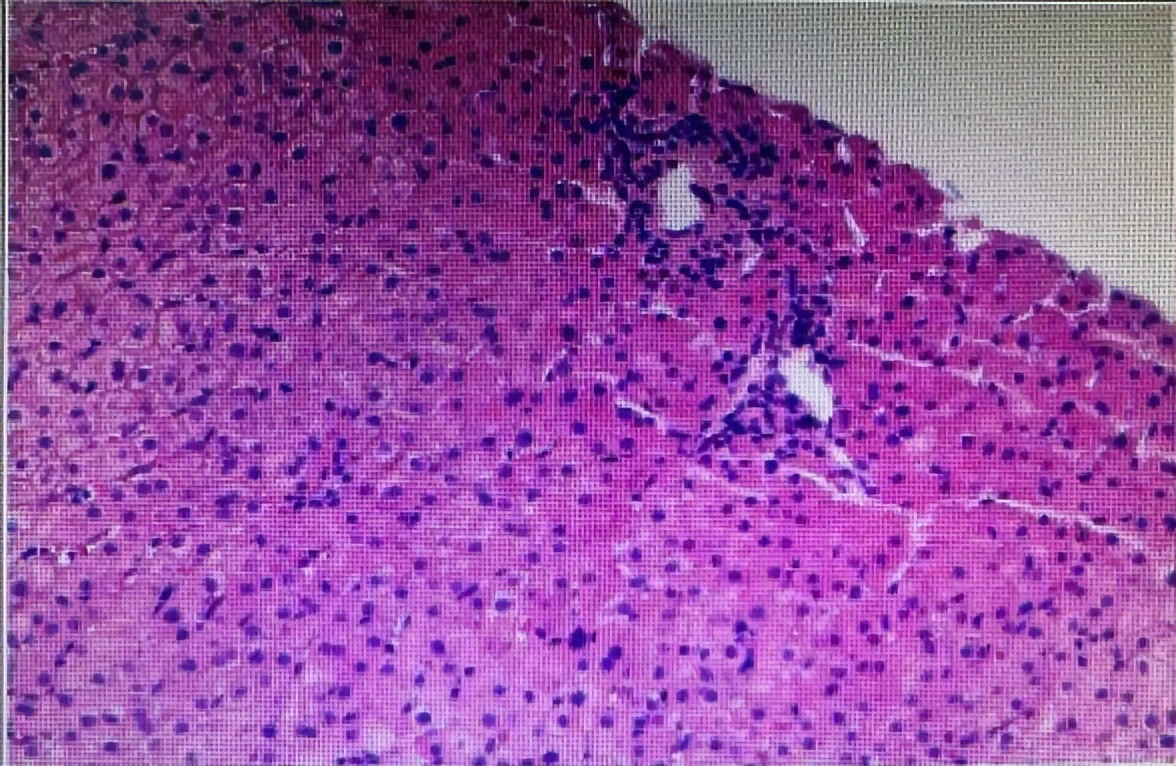

♦患者检查发现肝硬化、脾大、肝内外胆管未见明显扩张,食道静脉曲张。通过检查病理提示胆汁淤积性肝硬化:Masson染色显示肝硬化(100x);小叶间胆管减少和细胆管反应(CK7免疫染色);胆栓淤积与Mallory-Denk小体(H&E 400x);肝周细胞出现铜沉积(罗丹宁200x)。